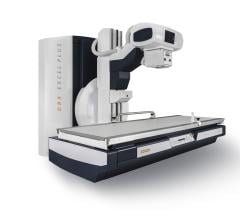

Image courtesy of EOS Imaging.

January 27, 2015 — EOS Imaging announced that the U.S. Food and Drug Administration (FDA) has cleared the Micro Dose feature of the EOS imaging system for pediatric imaging.

Micro Dose represents a breakthrough for patients with orthopedic conditions requiring frequent imaging exams for the continuous monitoring of disease progression and treatment. Initial results presented at the 2013 French Society of Radiology annual meeting (JFR 2013) and during the 2014 annual meeting of the Radiological Society of North America (RSNA 2014) concluded that Micro Dose generates dosage levels equivalent to a week of naturally-occurring background radiation in pediatric patients receiving 2-D and 3-D follow-up examinations.

Pediatric patients remain particularly sensitive to adverse effects associated with excessive exposure to radiation. Most notably, pediatric patients with scoliosis require frequent imaging sessions to monitor treatment progression, which can increase the risk of radiation-induced cancer later in life.